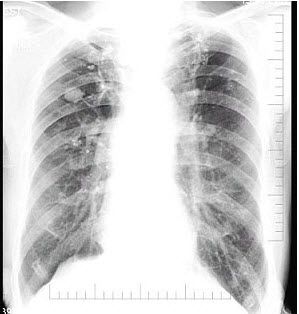

慢阻肺胸片

慢阻肺胸片,慢阻肺图片

慢阻肺图片

肺气肿胸片

慢阻肺胸片图片

慢阻肺x线

胸片肺气肿

慢阻肺